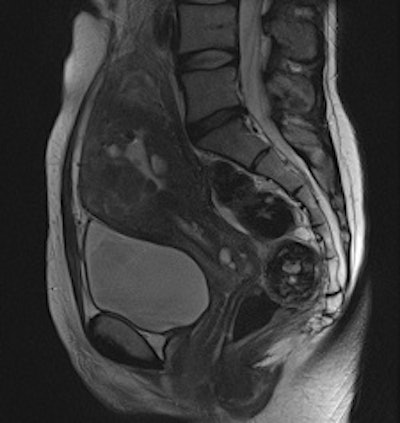

Adenomyosis and intramural leiomyomas: The intramural uterine changes, cervical structures, and bladder wall are more sharply delineated on the BLADE sequence (right); however, SNR and CNR are higher on the conventional T2-weighted image (left). There are also fewer motion artifacts in the surrounding tissue on the BLADE image."From a diagnostic point of view, the distinctive MRI properties of cystic structures are of primary importance when performing female pelvic imaging," they added. "Additional use of contrast showing enhancement of solid tumor components besides including conventional non-Cartesian sampled T1- and T2-weighted images into the protocol are advocated to facilitate the diagnosis and to avoid pitfalls."